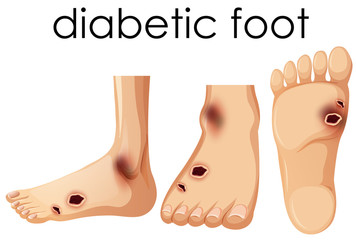

Qüestions sobre el pacient diabètic

- Quines complicacions poden patir els pacients diabètics?

- Quines cures es poden fer per prevenir el “peu diabètic”?